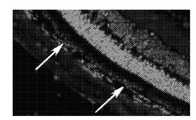

도 17은 돼지 안구에서 hESC-RPE 세포의 망막하 이식 후에 OCT 스캔, 적외선 영상 및 조직학적 영상을 도시한다.

17 shows OCT scans, infrared images, and histological images after subretinal transplantation of hESC-RPE cells in porcine eyeballs.